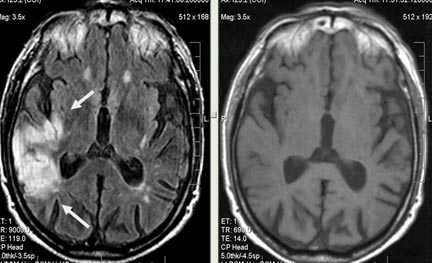

Лакунарное ишемическое ОНМК на фоне хронической сосудистой недостаточности.

Некоторые инфаркты при дисциркуляторной энцефалопатии протекают бессимптомно. Это «немые» инфаркты, которые, как правило, локализуются в глубоких отделах мозга и диагностируются только при МРТ. Этот случай показывает возможности выявление очага ограниченного ишемического ОНМК базальных ядер слева на фоне хронической ишемии.

Выраженная сосудистая энцефалопатия с наличием множественных очагов хронической ишемии, лакунарных постишемических кист. Программа ДВИ четко показывает фокус острого ОНМК в базальных ядрах справа на фоне лейкодистрофии.

Внутримозговая гематома (граница острой и ранней подострой стадий - 3 суток), осложнившаяся внутрижелудочковым кровоизлиянием.

Внутримозговая гематома, поздний подострый период (14-21 день) с перифокальным отеком вокруг гематомы.

Внутримозговая гематома правой теменной доли. Граница поздней подострой и ранней хронической стадии. В Т2-ВИ виден ободок гемосидерина (стрелка).

Хочется подчеркнуть возможность МРТ в выявлении последствий геморрагического поражения - остается хорошо дифференцируемый по Т2 ободок гемосидерина, недоступный для визуализации при других методах нейровизуализации.

Стрелками показан ободок гемосидерина по периферии постишемической кисты.